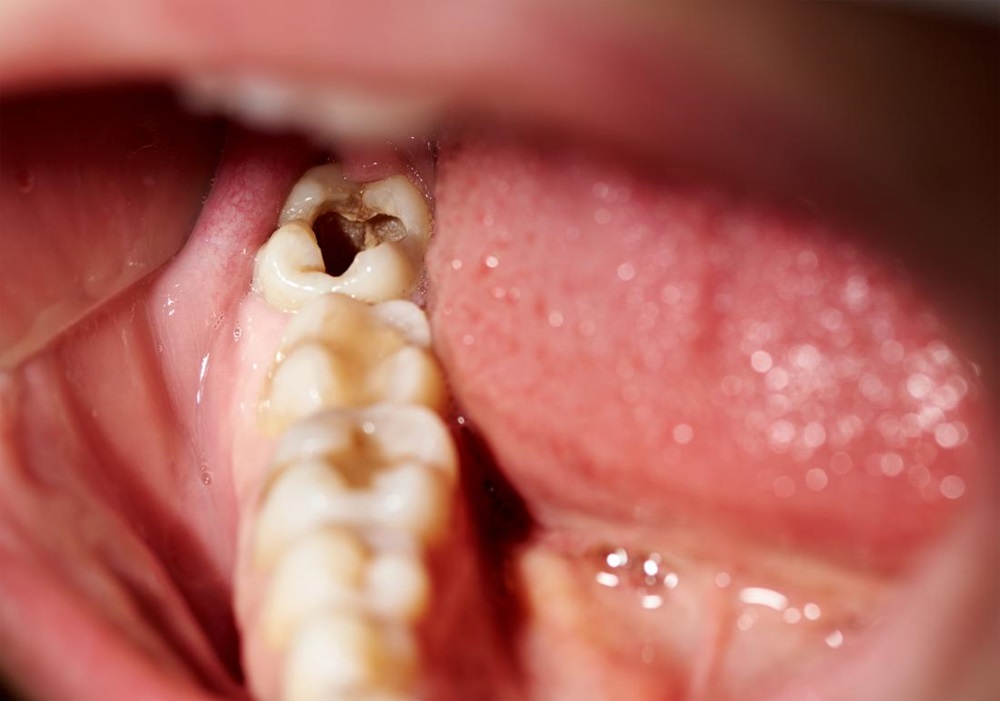

• Xuất hiện các đốm nâu đen trên bề mặt răng: Đây là dấu hiệu phổ biến nhất của sâu răng. Vi khuẩn tấn công men răng, gây mất khoáng chất và hình thành các lỗ rỗng trên bề mặt răng, thường xuất hiện dưới dạng các đốm nâu đen.

• Răng khôn cũng là răng hàm, có cấu trúc nhiều khe, kẽ và mặt nhai lớn. Do đó, thức ăn dễ bị mắc kẹt và tồn tại trong các kẽ răng, đây là môi trường lý tưởng cho vi khuẩn sinh sống, phát triển và dần dần tích tụ phá hủy men răng, dẫn đến tình trạng răng khôn bị sâu.